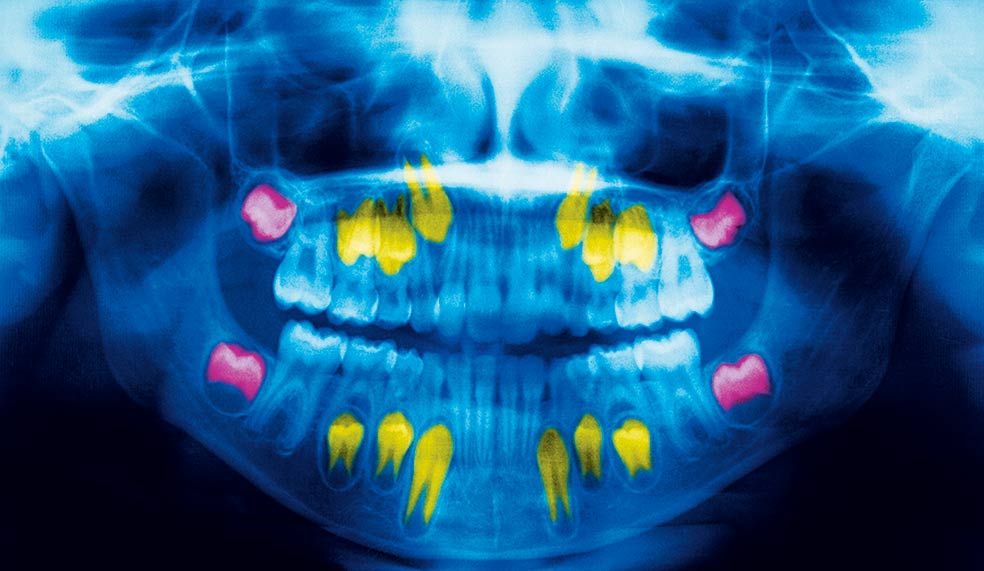

Un archivo en la boca. Dientes de leche (los blancos, salvo los cuatro incisivos superiores e inferiores, que ya son definitivos), permanentes en proceso de reemplazar a los de leche (amarillos) y segundos molares (rosas), los previos a que salgan las muelas del juicio. La dentadura informa de nuestras vivencias.getty images